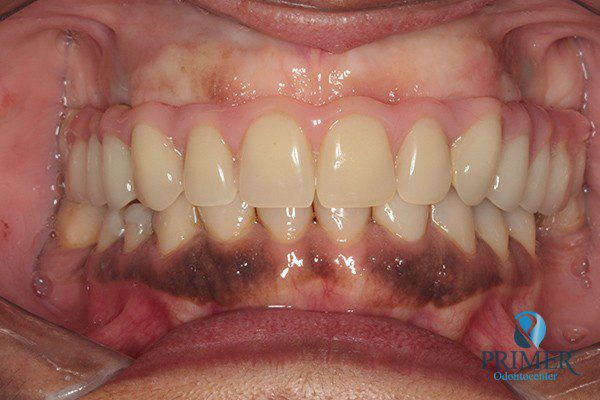

Realizado em: Agosto de 2012Detalhes do tratamento: Implantes instalados imediatamente após extrações de dentes inferiores e prótese fixa sobre implantes (instalada 72 horas após a cirurgia).

- Depois

- Sorriso final